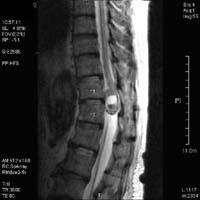

<Ç㸮µð½ºÅ©>

<¼ö¼úÀü>

<¼ö¼úÈÄ>

Á¦

4.5¹ø ¿äÃߺΠÃß°£ÆÇ Å»ÃâÁõÀ¸·Î ¼ö¼úÇÑ

ȯÀÚÀÇ ¿äÃß MRI¼Ò°ßÀ¸·Î ¼ö¼úÈÄ Å»Ãâ

µð½ºÅ©ÀÇ Á¦°ÅµÈ ¸ð½À°ú ÀûÃâµÈ µð½ºÅ©¸¦

º¼ ¼ö ÀÖ´Ù.